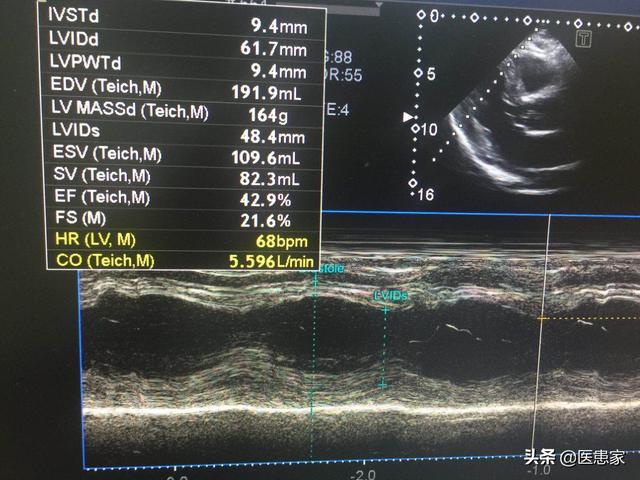

いわゆる心臓発作は、冠動脈の急性閉塞によって起こる壊死であり、その結果、心筋細胞は持続的な虚血と低酸素状態に陥る。急性心筋梗塞後、特に初日は心筋細胞の電気的活動が非常に不安定で、心室頻拍や心室細動などの悪性不整脈が起こりやすく、梗塞死の最も多い原因である突然死も起こりやすい。したがって、急性心筋梗塞の患者にはICUでの安静と心臓モニタリングが必要であり、これにより突然死のリスクを減らすことができる。

梗塞の大きさが大きすぎると、心原性ショックや急性左心不全などの重篤な合併症が起こり、救命が間に合わなければ死亡することもある。場合によっては心臓破裂などの重篤な状態に陥り、後戻りできなくなることもある。

抗凝固療法や抗血小板療法によって生命が助かったとしても、壊死した心筋では心筋リモデリングが起こり、心不全や心室壁腫瘍などの合併症を引き起こし、将来のQOLに影響を及ぼす。したがって、血行動態が安定している梗塞患者は、できるだけ早期に心筋リモデリングを抑制するACEIなどの薬剤を服用すべきである。

したがって、急性心筋梗塞の患者は、最初に120にダイヤルし、直ちに緊急PCIが可能な胸痛センターのグリーンチャンネルに行き、できるだけ早く閉塞血管を開き、瀕死の心筋を救い、心筋梗塞後の人体への致命的な危険を減らすべきである。緊急PCIができる病院に短時間(2時間)で到着できない場合も、できるだけ早く最寄りの病院で治療を受け、静脈路を開いて心臓の監視を行い、禁忌がなければ血栓溶解療法を行うべきである。